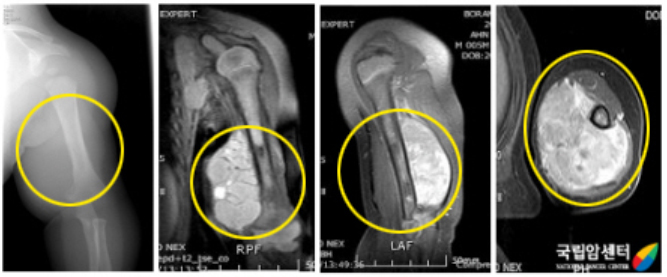

[ 자기공명영상(MRI) ]

연부조직종양을 판단하는 데 탁월한 검사입니다. 특히 종양의 병기(stage)를 결정하는 데 필수적인 검사로 종양과 주위 조직 특히, 혈관 및 신경과의 상관관계를 파악하는 데 중요한 검사입니다. 또한 종양에 대한 항암화학요법 전후에 영상을 비교하여 치료 효과 판정에 이용하기도 합니다. MR 분광기(spectroscopy)의 사용으로 종양실질의 구성 성분을 예측할 수 있어 진단에 도움을 줍니다.

[ 왼쪽 상완부에 횡문근육종을 가진 환아의 사진 ]

[ 위 환아의 항암약물치료 후 사진과 병리 사진 ]